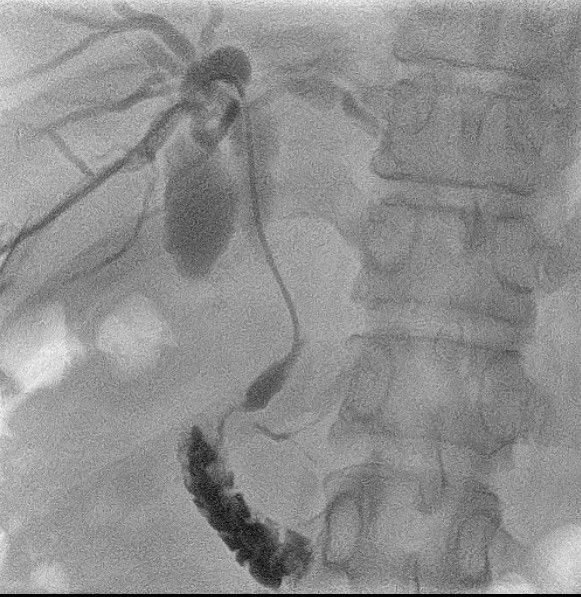

– Cholangiogram identified a tight stricture in the hepatic duct, CBD, and duodenum.

– Placement of a 10mm x 80mm SEM biliary stent with external drainage at the confluence.